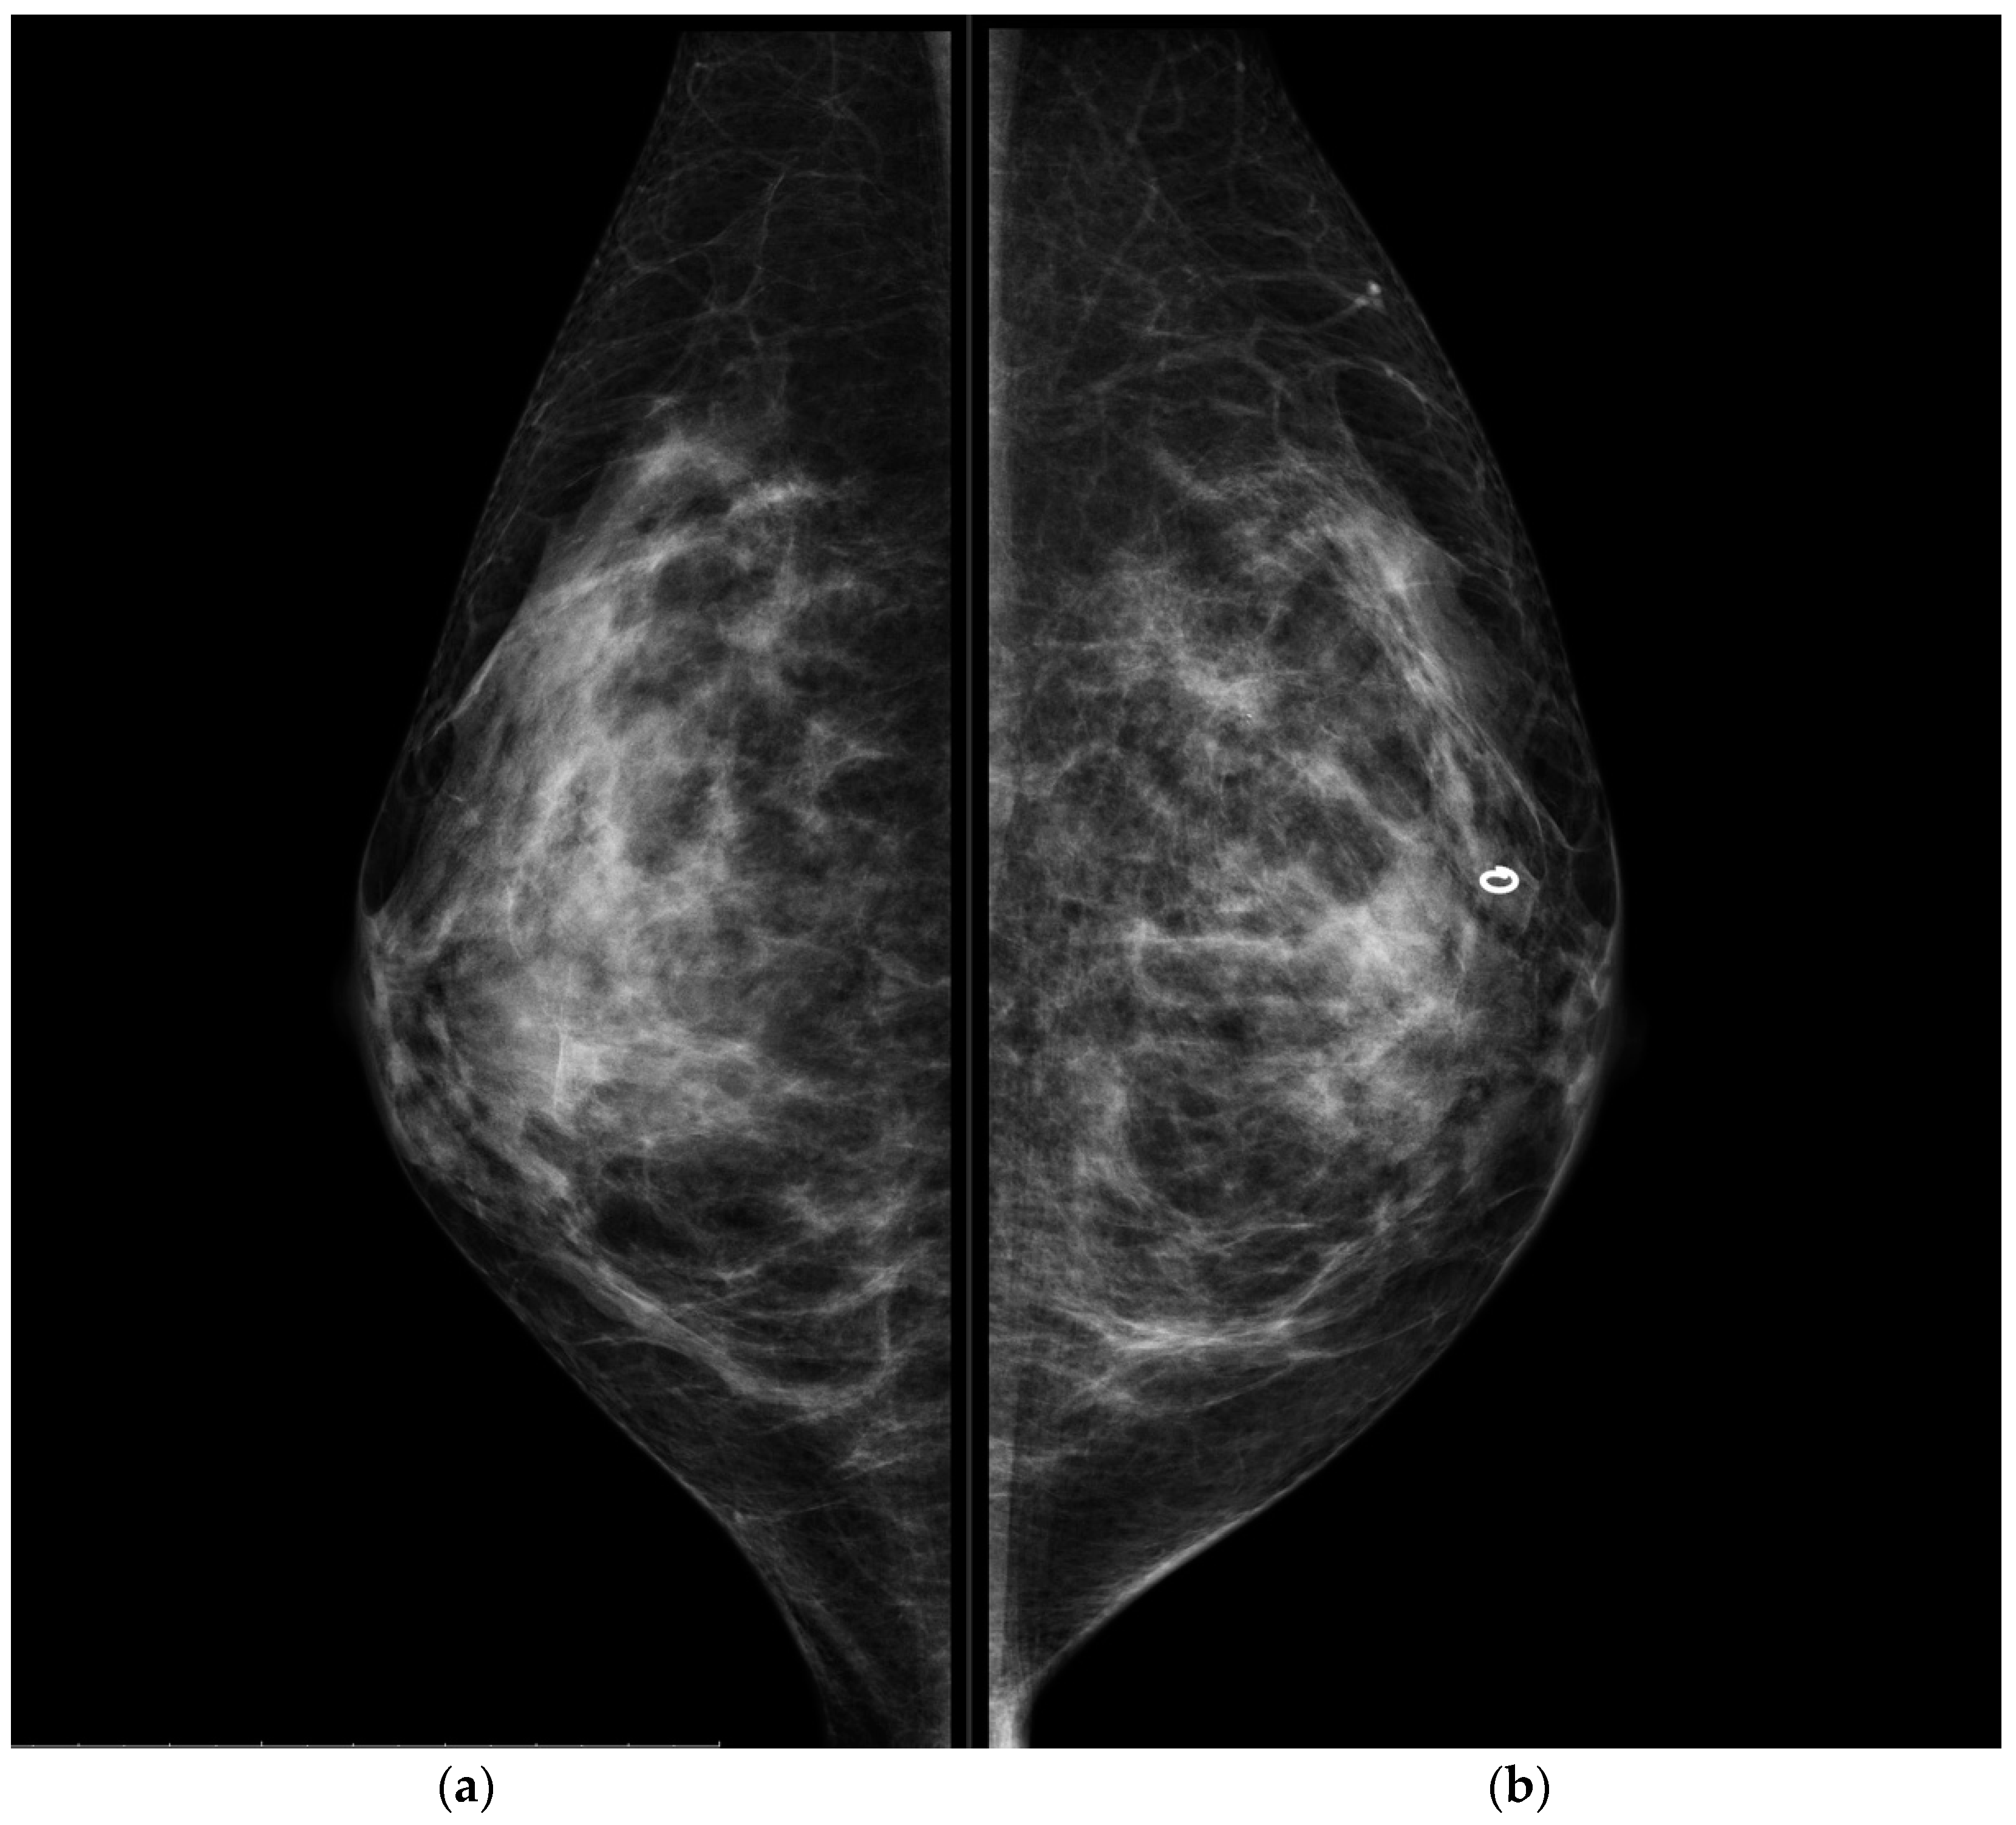

Figure 1. Conventional CC projections of the right breast (a) and left breast (b). A circular-shape marker released after US-guided biopsy was seen in the retro-areolar left breast. No suspicious mammographic findings were detected.

Breast ultrasound demonstrated some enlarged and suspicious axillary nodes (largest node dimension: 45 mm) and a small low-suspicious hypoechoic area in the retro-areolar left breast (BI-RADS 3). At mammography, no significant findings were found in both breasts.

CESM also confirmed the presence of a metallic marker in the left retro-areolar breast, previously released in the breast biopsy site (Figure 1, Figure 2, Figure 3 and Figure 4).